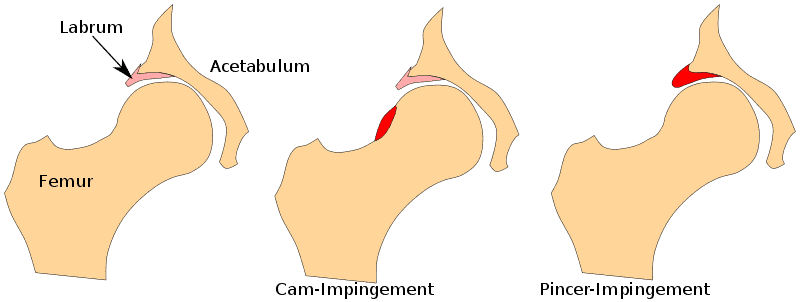

大腿骨寛骨臼インピンジメント(FAI)とは、股関節インピンジメントとも呼ばれ、寛骨臼および/または大腿骨頚部の形態的変化により、動作中に股関節唇が衝突することを指す。 大きく分けて2つのタイプがある: 大腿骨頭が大きすぎる場合はCAM形態(男性に多い)、寛骨臼リムが伸びすぎている場合はPincer形態と呼ばれ、女性に多い。 混合型では、CAMとピンサーの両方の形態が存在する。